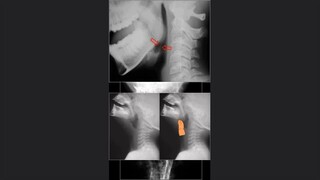

La valoración de la médula